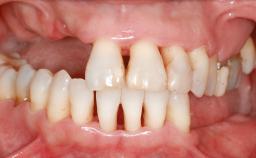

Replacement of Multiple Teeth in a Partially Dentate Posterior Mandible with a Fixed Dental Prosthesis Using a Flapless Approach

An 80-year-old female patient was referred to clinic for rehabilitation of her dentition. The patient’s medical history revealed no significant findings that would preclude routine dental and oral surgical procedures. She reported no drug allergies and was currently taking no prescription medications.

Her chief complaint was her inability to masticate efficiently due to the recent loss of her mandibular second premolars and first molars bilaterally. She expressed a desire for fixed prostheses in the shortest possible time due to her advanced age, requesting that replacement teeth should look as natural as possible. She was otherwise comfortable and not experiencing any symptoms from her teeth.